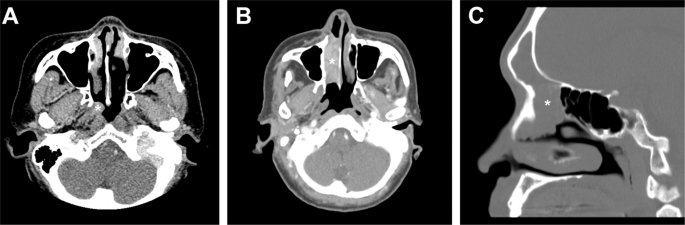

In the first step, we identified DEK-AFF2 fusions in three out of 14 initial cases, which included 11 in-house cases and three cases from the consultation files. In the second step, additional four LGPSCs were recruited and all tested positive for the DEK-AFF2 fusion. Three of the four cases were previously reported, including one case by Lewis et al. [4] and two cases by Zhai et al. (patients 4 and 5 in the original series) [9]. The clinical information of these seven cases is summarized in Table 2. There were five females and two males with a median age of 53 years (range: 28–79 years). The sites of initial presentation included the nasopharynx, nasal cavity, and paranasal sinuses (Fig. 1). One case (case 6) showed a very extensive regional involvement to the skull base and middle ear. All cases were initially diagnosed as SPs with or without dysplasia or carcinoma in situ (CIS) and were treated with local excision with or without adjuvant therapy. During the median follow-up of 26 months (range: 7 months to 18 years), all cases had at least one local recurrence. Two cases (case 4 and 6) developed nodal metastases. One case (case 4) had widely invasive tumor through multiple recurrences, and the patient eventually died of the disease 18 years after the initial diagnosis.

A Case 1 showed a tumor at right nasopharynx (asterisk) and superior turbinate. B Case 2 showed a tumor occupying right nasal cavity (asterisk). C Case 3 showed a tumor involving left frontal and anterior ethmoid sinuses (asterisk).